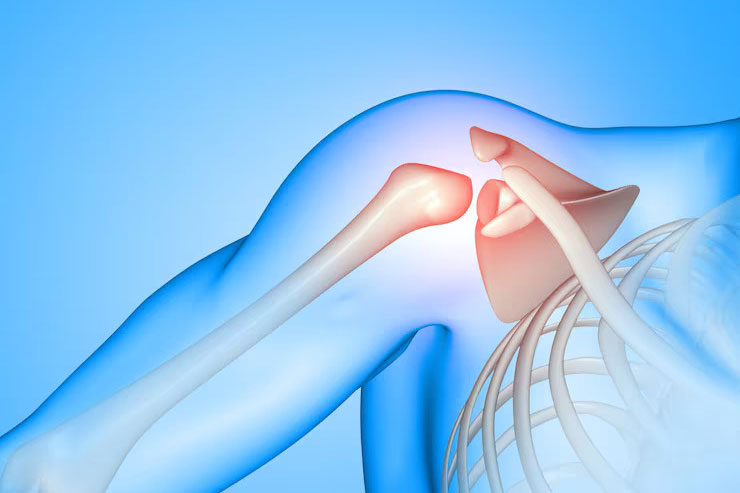

Dr. Shubham Agarwal is a highly respected and trusted orthopaedic surgeon in Jaipur, known for his expertise in orthopaedic surgery, sports injuries, arthroscopy, and joint replacement. He is currently serving as a Consultant Orthopaedics, Sports Injuries & Joint Replacement Surgeon at Nivik Hospital, Jaipur. With advanced training from prestigious institutions in India and abroad, Dr. Agarwal combines ethical medical practice with accurate diagnosis and evidence-based treatment. His clinical expertise includes knee and shoulder arthroscopy, ACL reconstruction, rotator cuff injuries, joint replacement surgery, and arthritis management. Committed to personalized care, Dr. Shubham Agarwal focuses on long-term recovery, pain-free mobility, and improved quality of life for his patients, making him one of the leading orthopaedic doctors in Vidhyadhar Nagar and Jaipur.